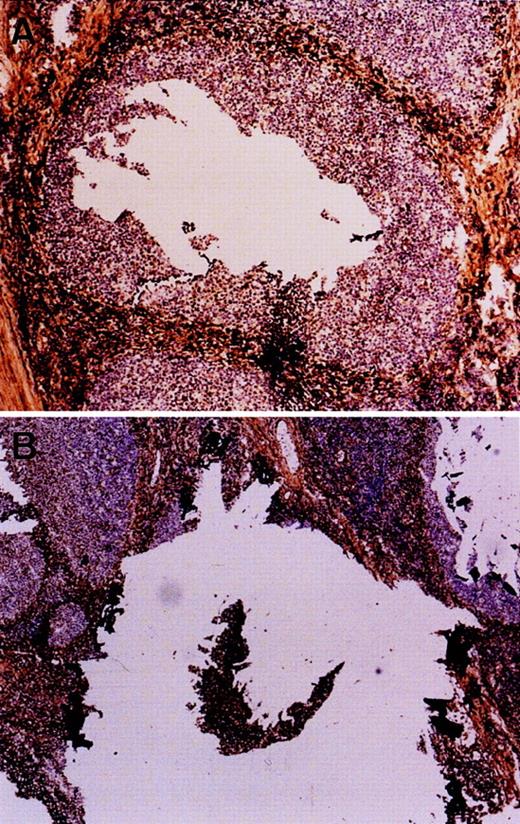

The percentage of malignant cells was estimated by histological examination. The follicular and mantle cell lymphomas contained at least 60% tumor cells, whereas most MALT lymphomas contained only 10% to 60% of tumor cells. For these latter cases, tumor cells were enriched by microdissection.10 Germinal center and mantle B cells were separately microdissected from a frozen section of tonsil immuno-stained for IgD (Fig 1). DNA extraction was performed as described elsewhere.10 11

Microdissection of germinal center (A) and naive B cells (B) of the mantle zone. Frozen sections of a tonsil were immuno-stained for IgD to highlight mantle cells. Germinal center cells were directly microdissected (the hole), whereas mantle cells were first isolated (the island) then harvested.